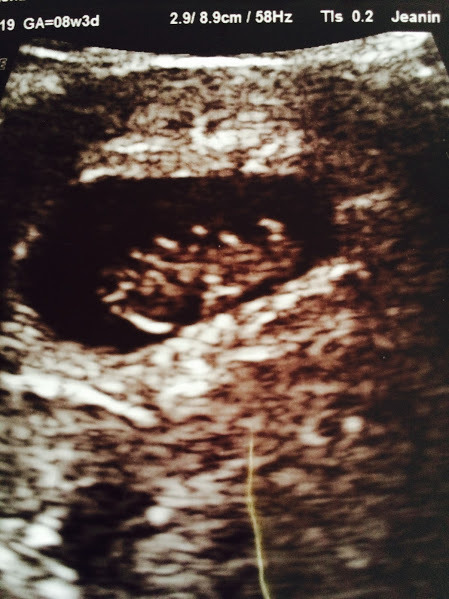

Please can I join? I am currently 8+6 with my 2nd DC but this one is an IVF baby. I was waiting until I had a good scan to join which we did on Sat - it was amazing to see.